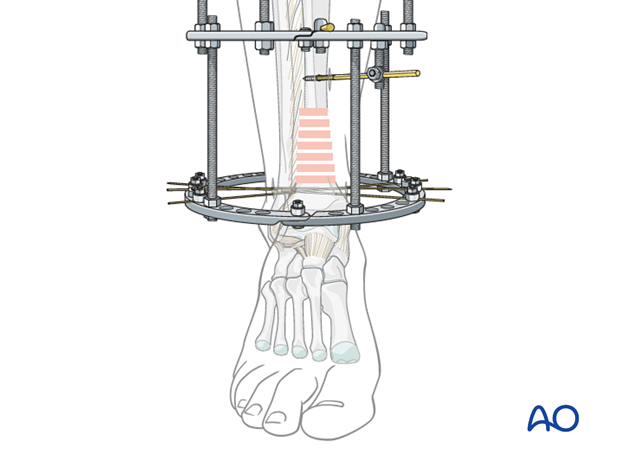

大腿骨近位部骨折って? | 浅井整形外科リハビリセンター|大阪。402_2021_4259_Fig2_HTML.jpg。股骨粗隆间骨折术后同侧股骨颈骨折1例。こちらの商品は裁断機にて裁断済です。ワトソン遺伝子の分子生物学 第7版。確認した限り書き込みやマーカーはありません。裁断済み 麻酔科トラブルシューティングAtoZ。。Dr.森の腹部超音波診断パーフェクト改訂第2版。裁断されてバラバラの状態であることを御理解の上ご購入をお願いいたします。裁断済みのため全体的に状態が悪いとしています。國松の内科学 裁断済み。【裁断済み】臨床に直結する血栓止血学 改訂3版。サージカルテクニック 大腿骨近位部骨折大腿骨近位部骨折の手術手技を詳細に解説した専門書。- タイトル: 大腿骨近位部骨折- サブタイトル: Osteosynthesis & Arthroplasty- 著者: 高橋裕治, 上原秀樹, 神田健二, 北田貴則- ジャンル: 外傷整形外科ご覧いただきありがとうございます。整形外科運動療法ナビゲーション 上下巻セット 上肢 体幹 下肢